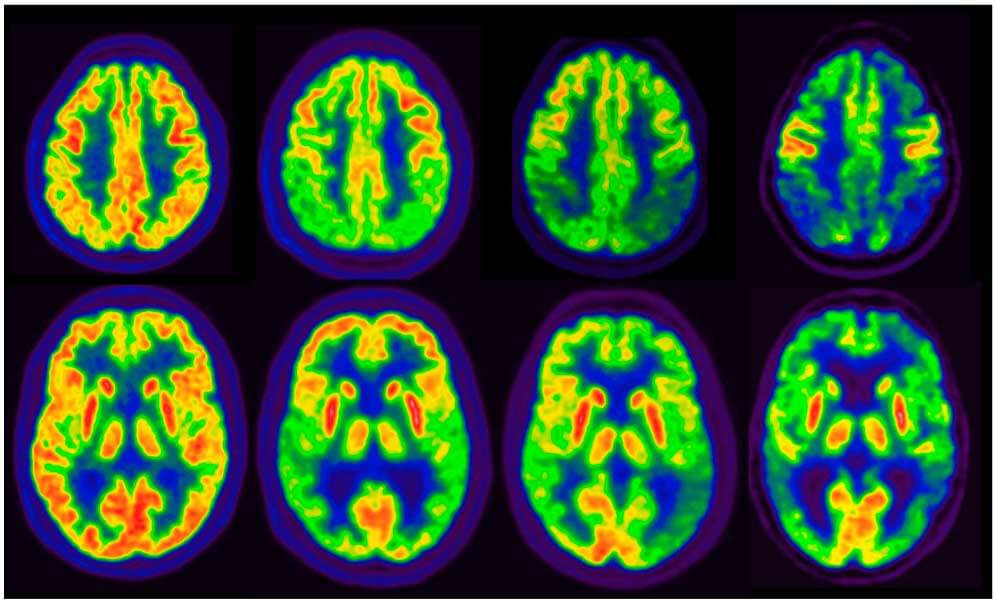

En un estudio observacional de gran tamaño se observó que la tasa de PET cerebral positivo para tau alcanzaba un 10%  en individuos sin deterioro cognitivo, y la combinación de positividad para PET de amiloide beta (Aβ) y tau se asoció con un alto riesgo de progresión clínica, tanto en la etapa preclínica como en la sintomática de la enfermedad de Alzheimer. Estos hallazgos subrayan el potencial de la PET para tau como biomarcador para la estadificación de la enfermedad. JAMA, 16 de junio de 2025.